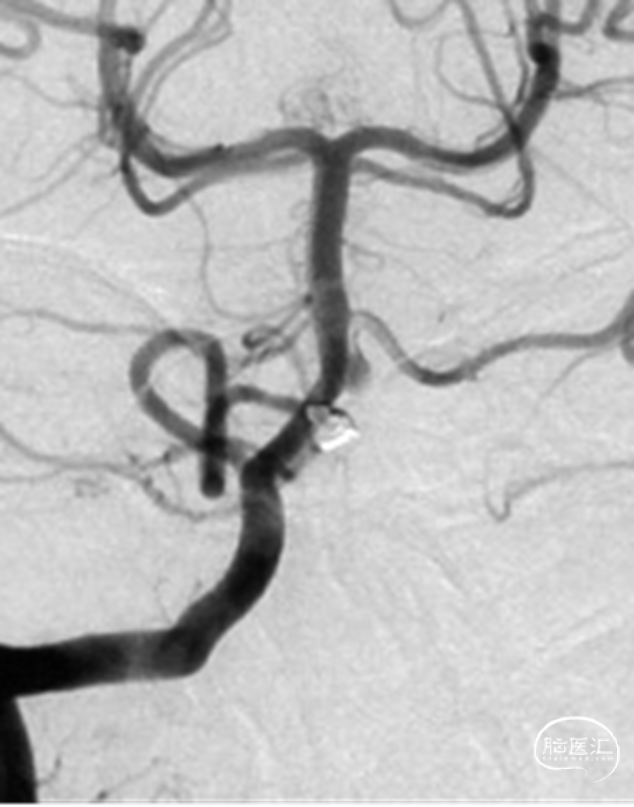

2、影像学随访:一年后的随访影像显示动脉瘤完全不显影。

一年后的随访影像